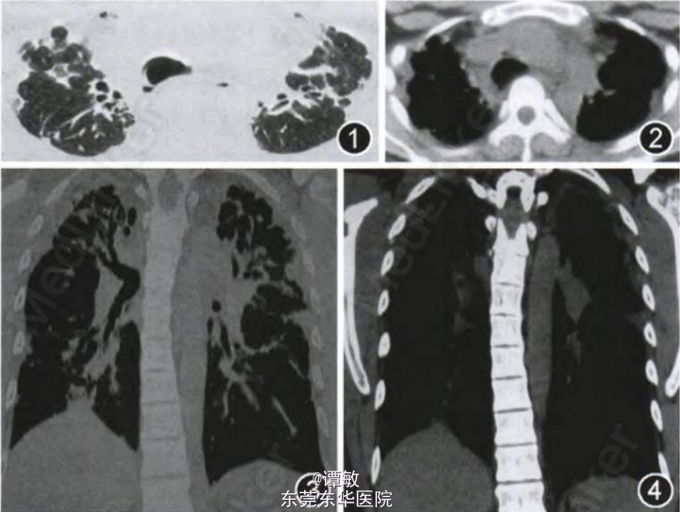

体检:患者双踝、双腕及双手掌指关节背侧、眉弓附近的红色斑疹,不高出皮面,局部有少量脱屑。双肺可闻及爆裂音、少许散在干鸣音。实验室检查:自然状态下动脉血气分析:pH值为7.425,PaCO2为38.7 mmHg,Pa02为85.6 mmHg.,HCO3- 为24.3 mmol/L。胸部高分辨率CT示胸膜增厚,分布以双上肺为主,胸膜下斑片、索条影,伴有牵张性支气管扩张(图1—4)。肺功能提示:“重度限制性通气功能障碍,伴弥散功能障碍”,FEV1/FVC为84.8%,FVC为1.29 L,占预计值%为26.5%,肺总量为2.31 L,占预计值%为33.1%,DLCO:4.12 mmol·min-1·kPa-1,占预计值%为36.5%。皮肤活检符合红斑角化症。余检查无异常。